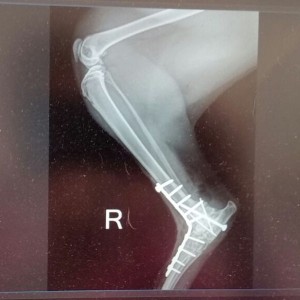

Katze Schnucki hatte leider nicht so einen guten Start ins Leben. Sie wurde in einem verwahrlosten Messi-Haushalt geboren. Niemand kümmerte sich so richtig um den Nachwuchs, und Schnucki entwischte dem Besitzer aus der Wohnung. Eine aufmerksame Nachbarin fütterte die scheue Katze und beobachtete eine seltsame Beinstellung bei Schnucki. Da Schnucki aber sehr misstrauisch war, bat die Frau den Katzenschutz Bonn/Rhein-Sieg e. V. um Hilfe. Wir haben nacheinander alle sechs Katzen inklusive Schnucki rausgeholt. Schnuckis Fehlstellung am Hinterbein entpuppte sich als ein alter Bruch. Sie konnte das Bein nicht richtig belasten, denn es knickte im Sprunggelenk weg. Schnucki wurde geröntgt, und wir standen vor der Alternative, das Bein abnehmen oder sie operieren zu lassen. Da sie noch eine junge Katze ist, haben wir uns für die Operation entschieden. Diese ist gut verlaufen. Schnucki muss noch ein paar Wochen in einer Box ausharren und kann dann endlich die Sonnenseite des Lebens ohne Einschränkungen genießen. Die Behandlungskosten belaufen sich auf ca. 1.500 € und reißen ein großes Loch in unsere Katzenkasse. Deshalb ist Schnucki auf Ihre Hilfe angewiesen: Möchten Sie uns bei der Bewältigung dieser Kosten helfen und uns unter dem Stichwort: „OP-Kosten für Schnucki“ unterstützen? Jeder noch so kleine Betrag hilft uns weiter!